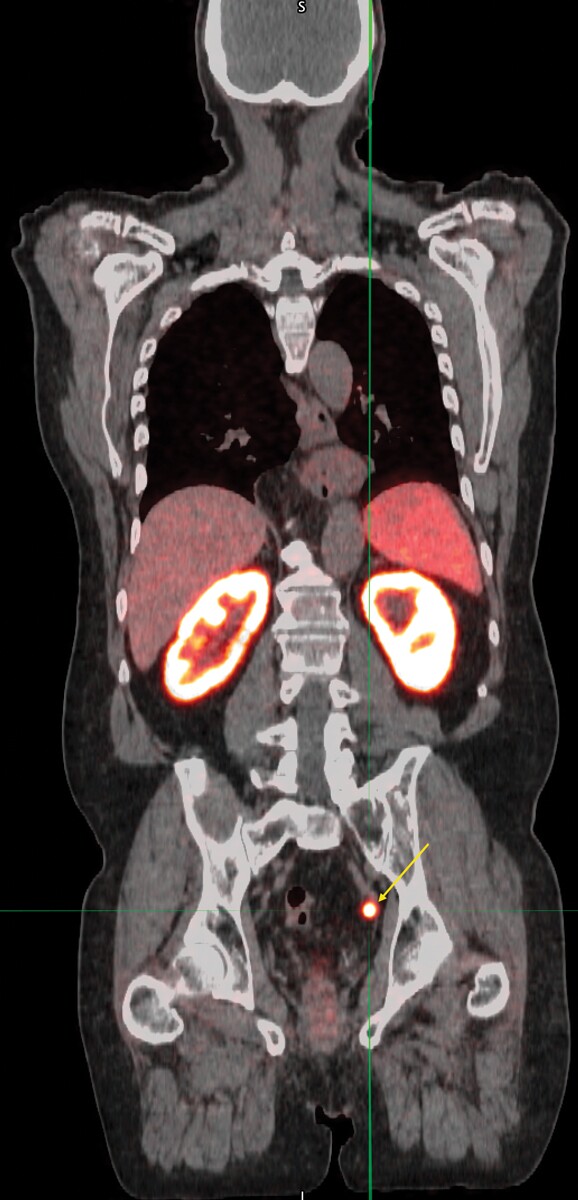

Most diseases manifest with biochemical signatures well in advance of anatomical changes. The image below shows a hybrid positron emission tomography/computed tomography (PET/CT) scan of a prostate cancer patient. The average-sized lymph node in the pelvis indicated by the yellow arrow would look normal in an anatomical image from a CT or magnetic resonance imaging (MRI) scan. But the PET scan shows, definitively, that the lymph node has been invaded by cancer cells: Before the scan, the patient was injected with a positron-emitting radiopharmaceutical that binds to an antigen found on the membranes of prostate cells, both normal and cancerous. PET imaging with disease-specific radiopharmaceuticals is dramatically changing the management of cancer through its remarkable sensitivity in detecting even tiny, remote tumors.

(Image courtesy of the University of Iowa department of radiology.)